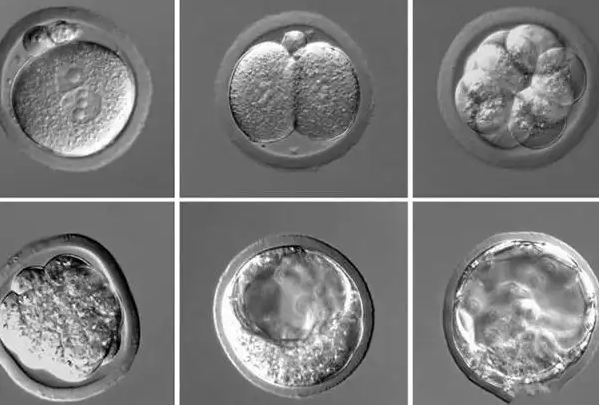

理解3bb和4bb的差异,需先掌握囊胚等级的通用标准。囊胚等级通常由“数字+两个字母”组成,数字代表囊胚的扩张和孵化程度(1-6级),第一个字母代表内细胞团(未来发育为胎儿)质量(A-C),第二个字母代表滋养层细胞(未来发育为胎盘)质量(A-C)。

其中,数字越大表示囊胚发育越成熟:3级代表囊胚腔完全充满胚胎,胚胎总体积变大,透明带变薄;4级代表囊胚腔扩张,胚胎体积增大导致透明带进一步变薄,部分胚胎开始与透明带脱离。而“bb”则是统一标准:内细胞团(第一个b)细胞数目少但排列紧密,滋养层细胞(第二个b)排列松散、数量偏少,但均满足基本移植要求。

3bb和4bb的核心差异集中在“发育阶段”,这直接影响着床潜力的表现。从发育程度看,3bb处于“完全扩张期”,囊胚腔刚充满胚胎,形态相对紧凑;4bb处于“扩张期”,囊胚腔进一步扩大,胚胎更饱满,与透明带的连接更松散,着床时突破透明带的阻力更小,理论上着床速度可能稍快。